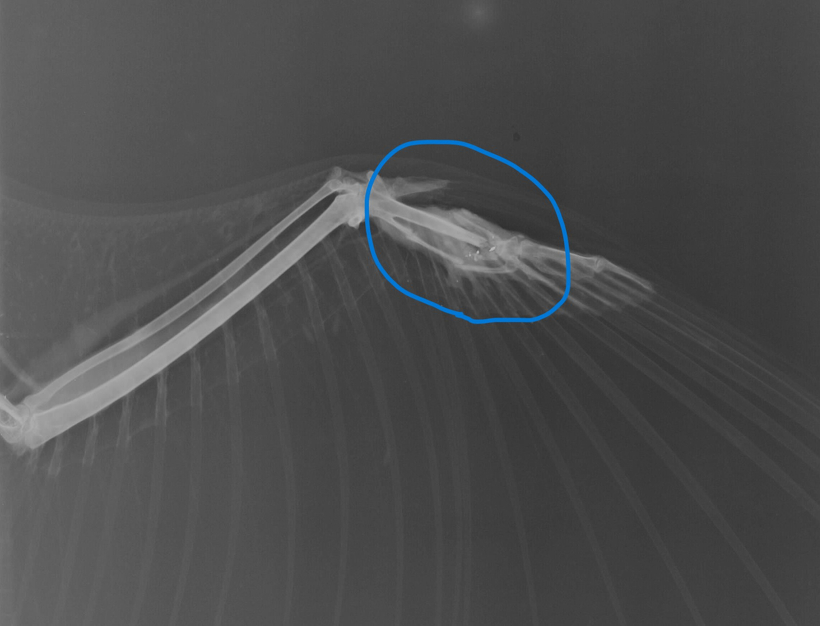

10月15日、高知空港近くで飛べないトビが保護されました。レントゲン検査の結果、右翼の手根部が骨折しており、ガリガリに痩せていました。